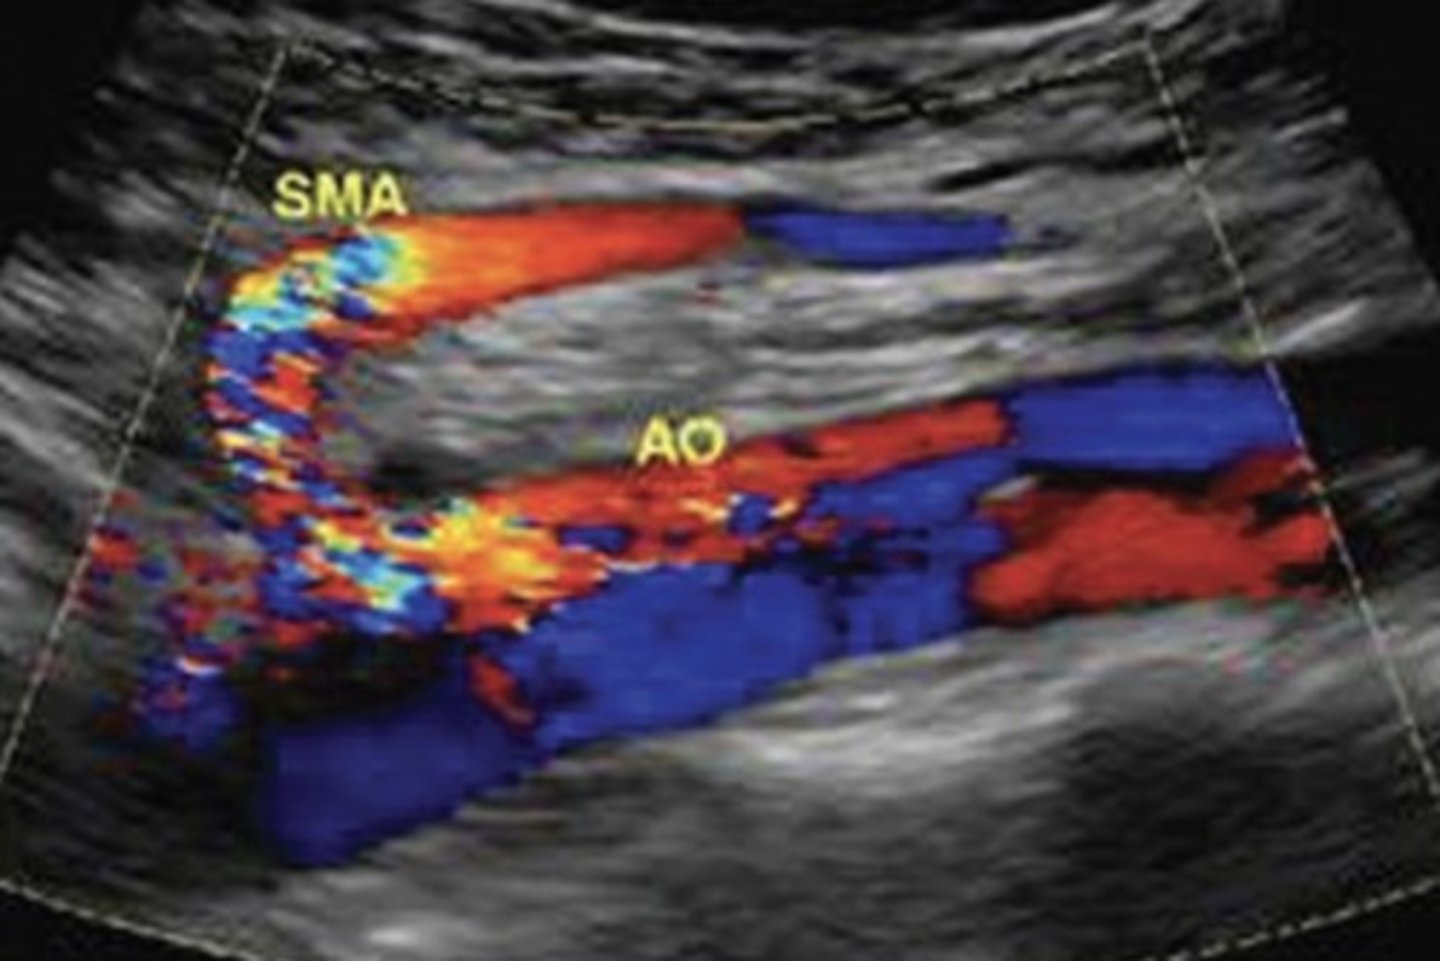

Common Trunk Variant

Celiac and SMA come off common trunk